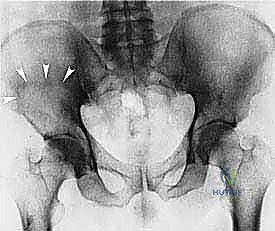

- Plain Radiography (FIG 2): While of limited value for early lesions, it provides an initial overview. As you can see in Figure 2A, we have a large lytic lesion of the right periacetabular region. Figure 2C shows a cartilage-forming lesion in the left ilium. However, plain films often underestimate the true extent of these tumors.

* CT with Intravenous Contrast and 3D Reconstruction (FIG 3): This is our workhorse for assessing bone involvement, destruction, and the critical relationship between the tumor and major pelvic blood vessels. It reveals any distortion of the pelvic anatomy and guides resectability. Figure 3A clearly shows extensive bone destruction and tumor extension into the pelvis and gluteal region. Figure 3C highlights an extensive tumor on the medial aspect of the ilium with destruction of the inner table.